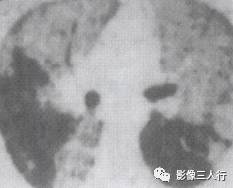

由于实变的肺组织与含气的支气管相衬托,在实变区中可见透明的支气管影即空气 支气管征,临床常见于大叶性肺炎的实变期,包括红色肝样变及灰色肝样变期,表现为密度均匀的致密影内可见透明的支气管影(图1)。这一征象被认为是肺泡炎性病变的有力证据。 医学百科网 | YxBaike.Com